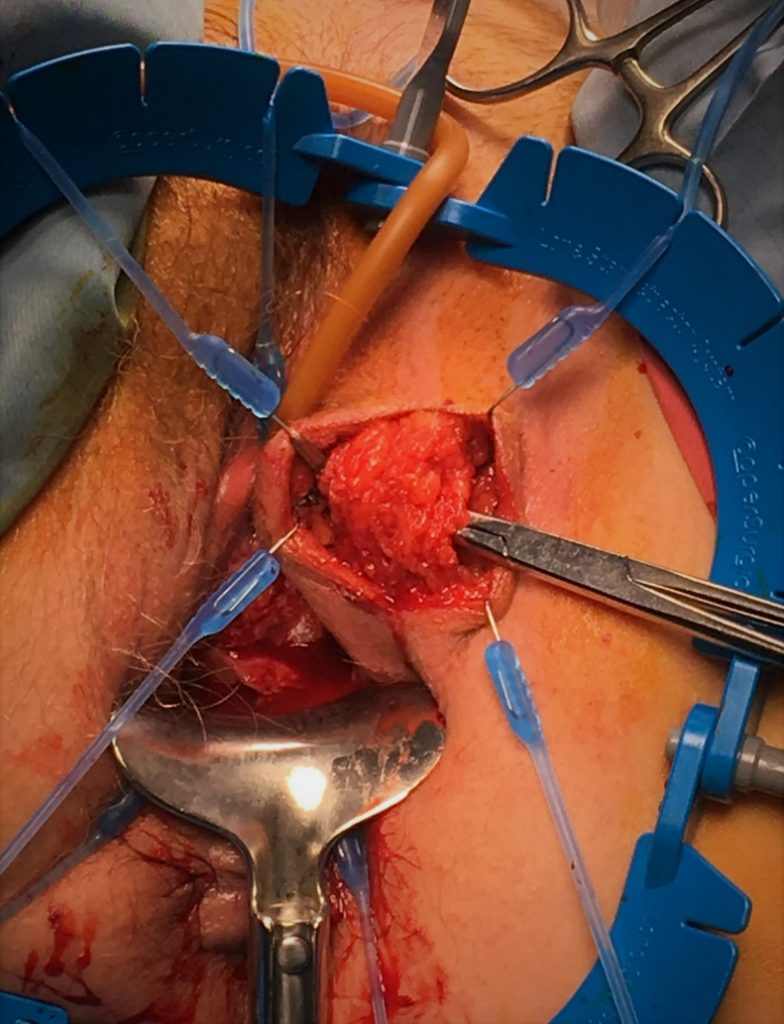

Se instala mediante una incisión perineal, con apertura del músculo bulboesponjoso y liberación circunferencial de la uretra bulbar (generalmente proximal o media), donde se instala el manguito. El balón regulador se instala en la región inguinal, en el espacio pre-peritoneal. La bomba se instala a través de esta última incisión, disecando en forma subcutánea hasta instalarla en el escroto. El dispositivo se activa a las 4-6 semanas.

Aunque se ha descrito la colpocleisis parcial sin resección del trayecto fistuloso (técnica de Latzco), la técnica más utilizada es la resección de la fístula (Video 3). Después del posicionamiento en litotomía y la visualización de la fístula (Figura 21), se realiza una resección del tejido vaginal incluyendo el trayecto fistuloso (Figura 22). La vejiga se repara luego en dos planos invaginantes con material reabsorbible 3-0 o 4-0 (Figura 23) y posteriormente la vagina se cierra en un tercer plano con un material similar. Se puede interponer un colgajo de grasa de labio mayor con la técnica de Martius si se considera necesario, por ejemplo, en fístulas complejas (Figura 24).55

La técnica transvesical (de O’Connor) se basa en una cistotomía amplia desde el domo vesical hasta llegar a la fistula por posterior, con adecuada visualización y eventual cateterización de los uréteres (Figura 25). Se debe realizar una cuidadosa disección del plano vesicovaginal (Figura 26). Cierre de la pared vaginal con material reabsorbible 3-0 y luego cierre de la vejiga con similar sutura (Figura 27). Se puede además movilizar un colgajo de peritoneo o epiplón que se interpone entre ambas suturas.